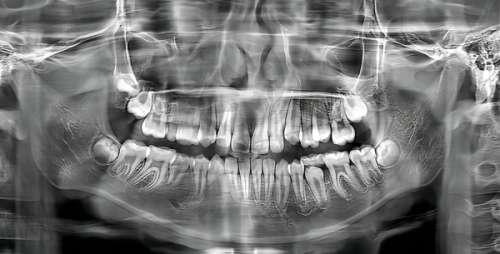

实例一:李先生,50岁,因牙齿缺失多年影响咀嚼和美观,来到深圳泰康拜博口腔门诊部(华强北店)。院长李满园为其进行了详细的检查和评估后,决定采用数字化种植牙技术进行全口种植。手术过程顺利,创口小,李先生术后修复快,疼痛感较轻。经过一段时间的修复,李先生重新拥有了健康的牙齿,咀嚼功能得到了极大改善,面容也更加饱满,他对治疗成效非常满意。